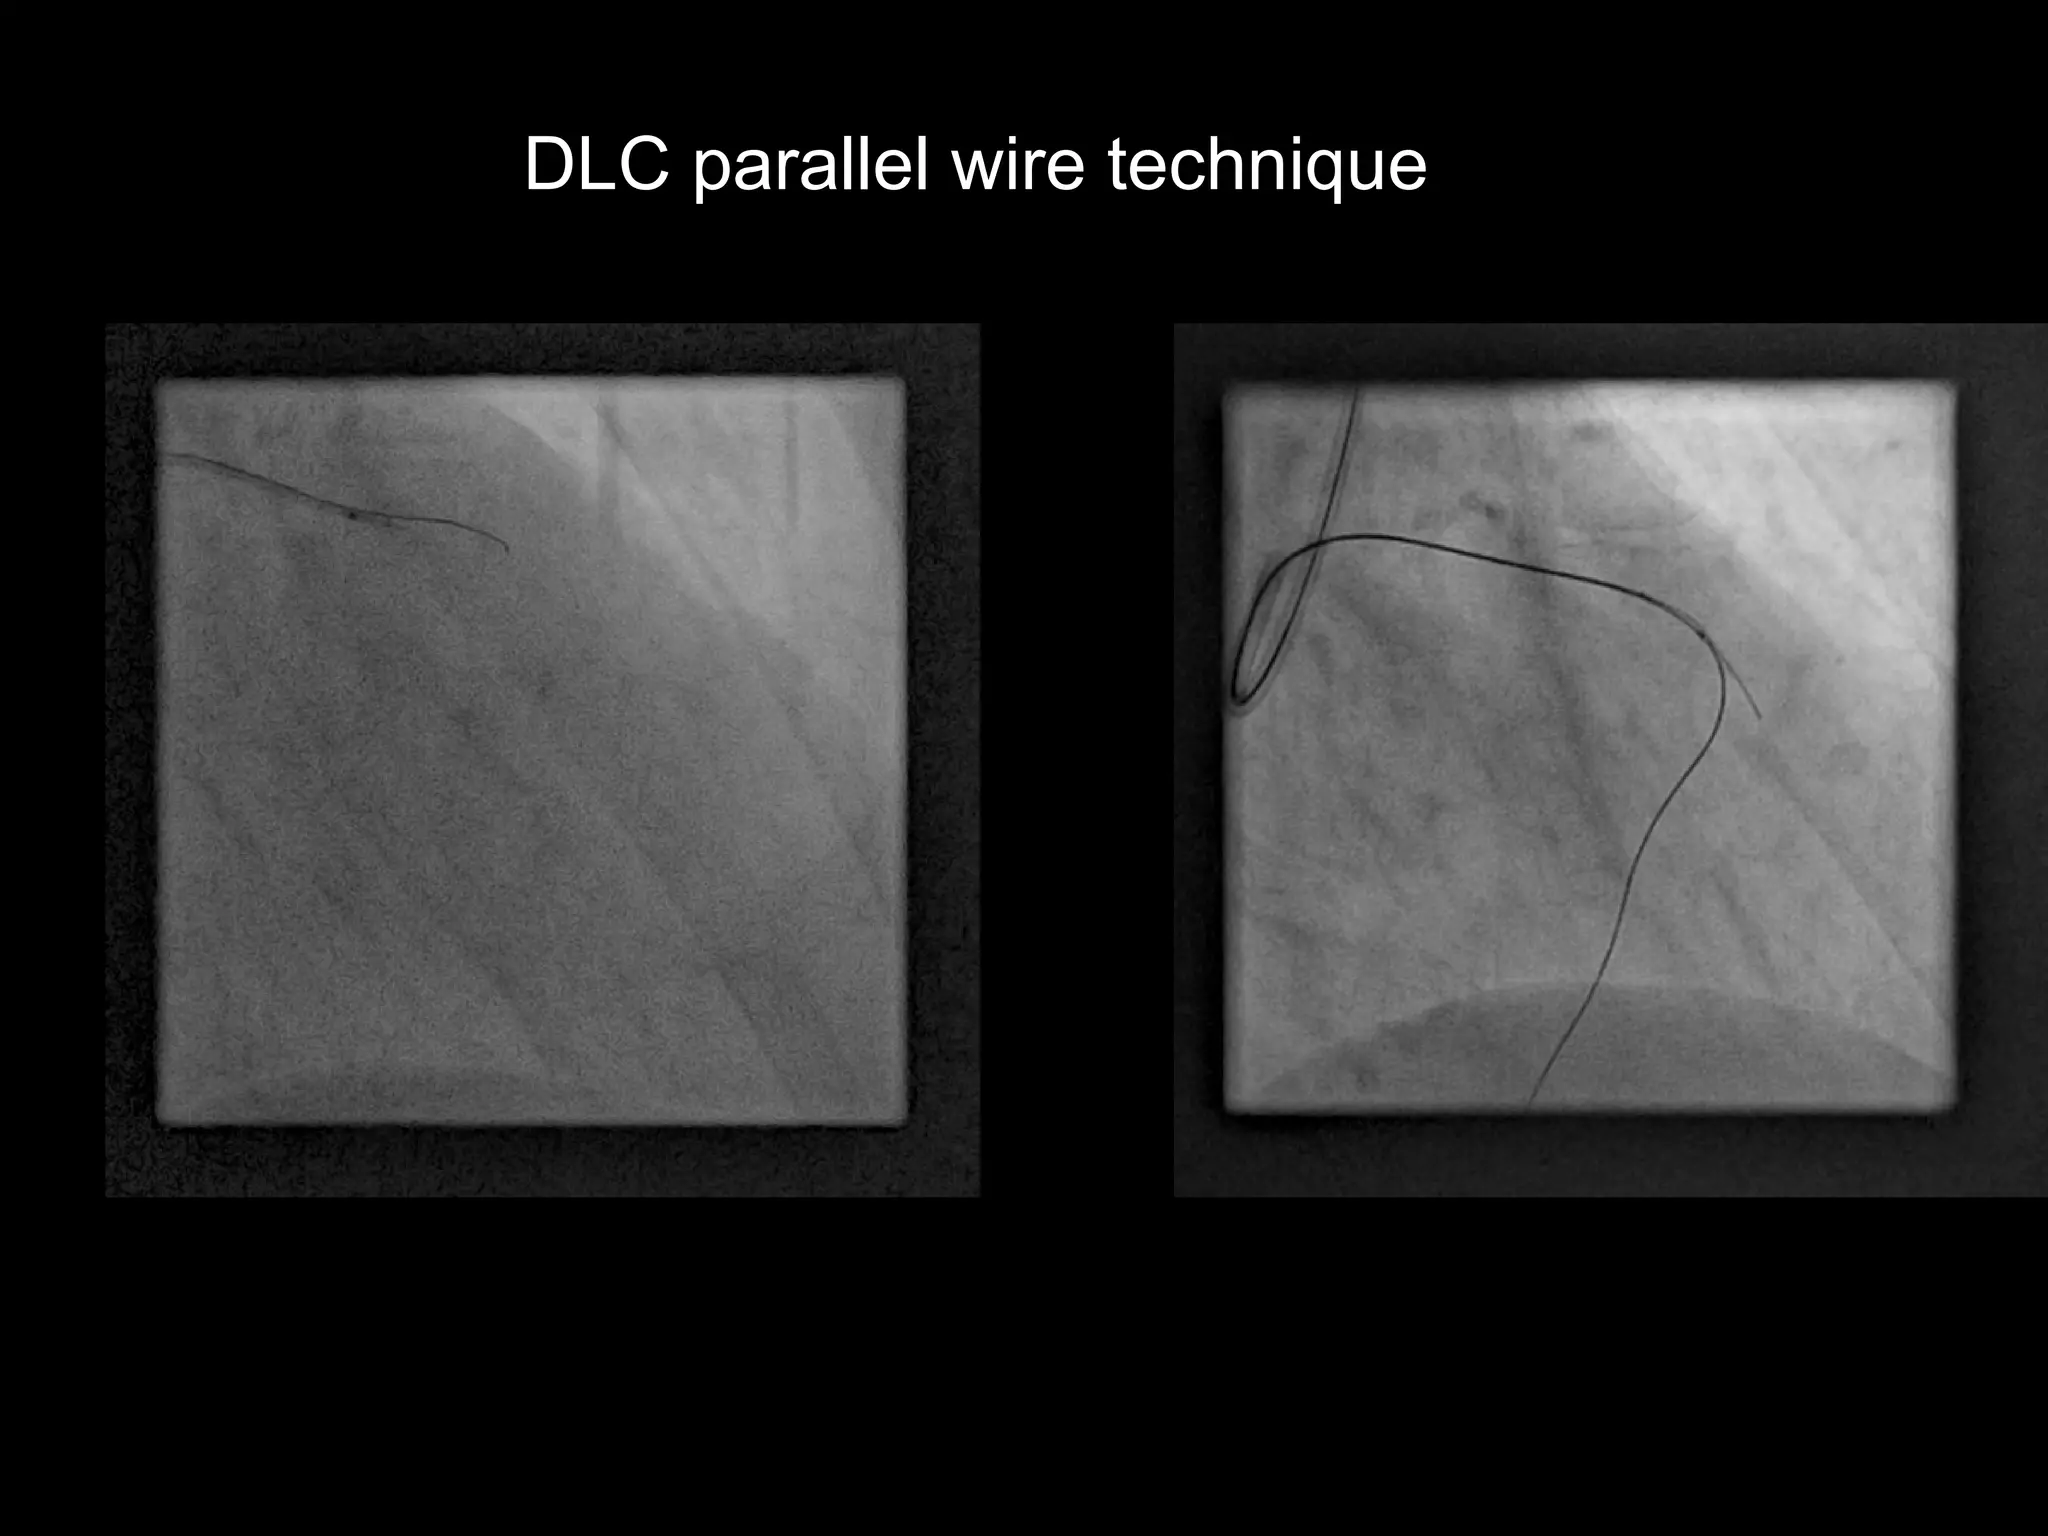

DLC parallel wire technique